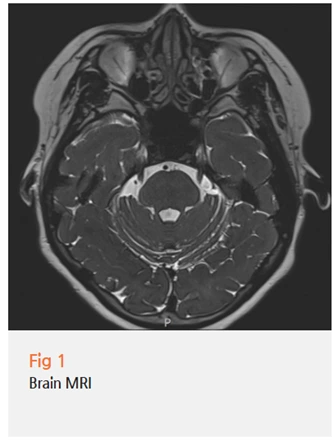

✔️ 뇌 MRI - 뇌에 문제가 있는지, 혹시 뇌종양이나 혈관 압박은 없는지

검사 결과, 뇌에는 문제가 없었어요.

그런데 목 쪽, 즉 경추부에 구조적인 문제가 확인됐어요.